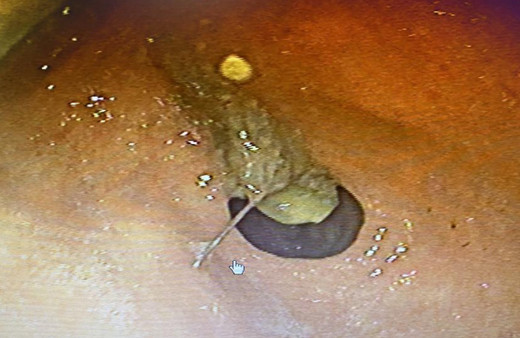

Mide